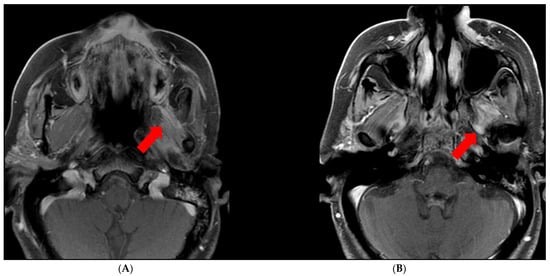

There are several technical considerations to keep in mind when assessing for perineural spread. Incomplete fat suppression can occur, especially at the air–bone interface, which can falsely suggest perineural enhancement. It is also important to note that there are parts of the cranial nerves that normally enhance due to perineural venous plexus accompanying the nerves, including the geniculate ganglion, proximal greater superficial petrosal nerve (namely the tympanic and mastoid segments [14]), and the proximal segments of the trigeminal nerves. Denervated muscles demonstrate enhancement and edema, which can have a mass-like appearance and may falsely suggest a mass in that region (Figure 2). Additionally, other entities can mimic PNTS, including infection, inflammation, ischemia, trauma, and demyelinating processes [15].

Figure 2.

Muscle denervation edema/enhancement. (A) Asymmetric enhancement of the left muscles of mastication due to denervation (arrow). (B) PNTS along the left V3 (arrow).